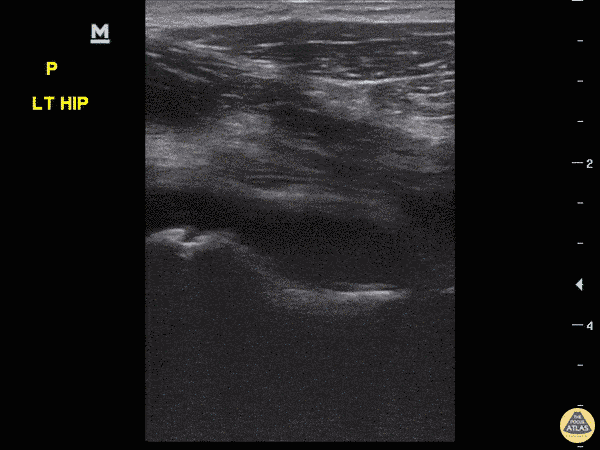

Pediatrics - Hip Effusion

8-year-old female with fever and upper left thigh pain starting last night. Refusing to bear weight and will not flex hip, discomfort with rotating hip. POCUS performed, revealed effusion. Still image comparing sides confirms effusion. Etiology of effusion remained uncertain. Dr. Sathya Subramaniam, Pediatric EM Fellow - Kings County/SUNY Downstate